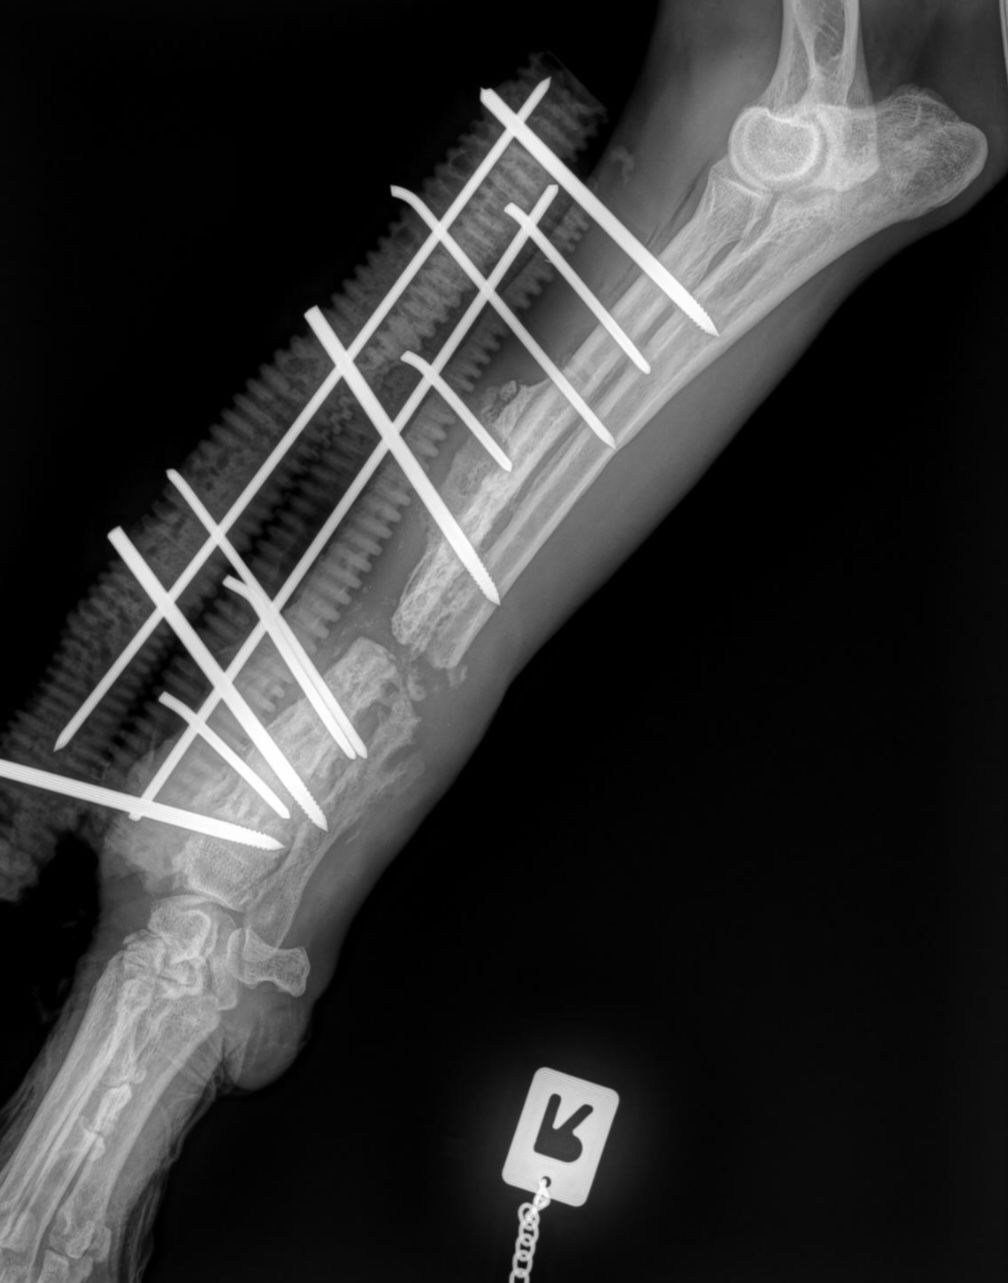

Der Knochen sieht katastrophal aus (Siehe aktuelle Röntgenbilder):

Eine Amputation ist hochwahrscheinlich.

Aurelia musste operiert werden. Sie hatte zahlreiche Bissverletzungen und ihr rechter Unterarm wurde gebrochen, sowohl Elle als auch Speiche.